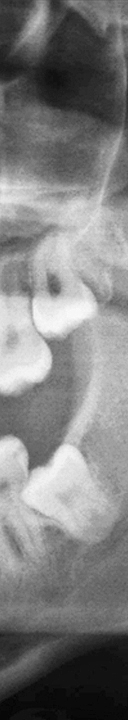

또한 사랑니가 삐뚤어지게 자라거나 매복 되어 있는 경우에는 더욱 더 심각한 문제를 일으킬 수 있었어요. 올바르게 자라지 않아 정상적으로 위치하고 있는 주변 치아에 영향을 주게 되어 치아 배열이 불규칙해질 수 있으며 또한 수평으로 누워서 잇몸에 완전히 덮여 사랑니가 아예 보이지 않는 경우, 또는 일부분만 덮여 있는 부분 매복처럼 다양한 형태로 나타날 수 있었어요. 사랑니가 매복 되어 있는 경우에는 염증이 생길 수 있어 볼, 편도선, 림프절 등이 부어올라 극심한 통증을 느끼게 되었어요. 또한 매복 되어 있는 사랑니의 형태가 심각한 경우에는 턱 뼈의 변형까지 생길 수 있었어요.

이처럼 사랑니는 여러가지 문제를 일으켜 치아 건강을 악화 시킬 수 있으니 대부분의 치과에서는 사랑니 발치를 권해드리고 있었어요. 하지만 사랑니가 매복 되어 있는 경우 신경과 가까운 곳에 사랑니가 위치하고 있기 때문에 발치를 하는 과정에서 신경을 건드릴 수 있어 숙련된 의료진에게 치료 받는 것이 중요하였어요.

매복 사랑니의 경우 발치 시간도 많이 걸리고 주변 신경을 건드리지 않고 발치를 해야 하기 때문에 난이도가 있는 시술로 부작용이 생기지 않게 치료 받는 것이 중요하므로 신경 위치와 주변 치아의 상태를 정밀하게 검사 가능하고 숙련된 실력으로 사랑니 발치를 할 수 있는 의료진이 있는지 꼭 확인하신 후 치과를 선택하시기를 바라겠어요.

신논현역치과에서는 3D CT 장비로 촬영을 하여 사랑니의 매복 상태와 사랑니 부근의 신경처럼 중요한 부분을 정밀 검사를 통해 확인하고 사랑니 발치에 대한 안전한 치료 계획을 세운 후 발치를 진행하고 있었어요. 개인 구강의 상태에 따라 사랑니의 모양, 매복 형태 및 정도가 모두 다르기 때문에 아름드리에서는 그에 알맞는 방법으로 사랑니 발치를 환자 구강 상태에 맞게 진행하고 있었어요.

무조건적인 발치에만 중점을 두고 치료하는 것이 아니라 환자의 구강 상태를 고려하여 사랑니 발치를 진행하고 있었어요. 특히 여러가지 유형으로 매복 되어 있는 사랑니의 경우 잇몸을 절개하여 치아를 꺼내야 하기 때문에 필요에 따라서는 치아를 조각 내거나 부셔서 제거해야 하고 발치 이후에는 절개한 잇몸을 봉합과 소독을 진행해야 했어요.

그렇기 때문에 신논현역치과는 환자의 구강 상태, 사랑니의 위치, 형태 등을 꼼꼼하게 분석하고 효율적이면서도 안전한 방법으로 꼭 필요한 부분만 최소 절개하여 사랑니 발치로 인해 생길 수 있는 위험 요소를 줄이고 회복 속도를 높일 수 있도록 안전하게 치료를 진행하고 있었어요.